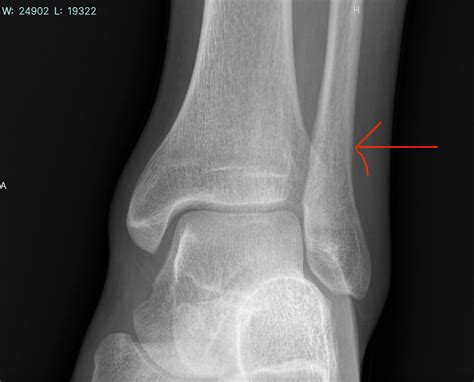

The fibula is the thin, long bone located on the lateral (outer) side of the lower leg. While it does not bear the majority of your body weight—the tibia carries most of it—the fibula serves as a crucial anchor point for various muscles that control ankle stability and foot movement. A Fibula Stress Fracture occurs when the bone is subjected to repeated force faster than it can remodel and repair itself. Over time, these tiny, microscopic cracks accumulate, leading to structural weakness.

• Point tenderness, where the pain is centralized in one specific spot along the fibula bone.

If you find that the pain persists for more than two weeks despite taking rest days, it is highly recommended to seek a professional medical evaluation, such as an X-ray or MRI, to confirm the diagnosis.